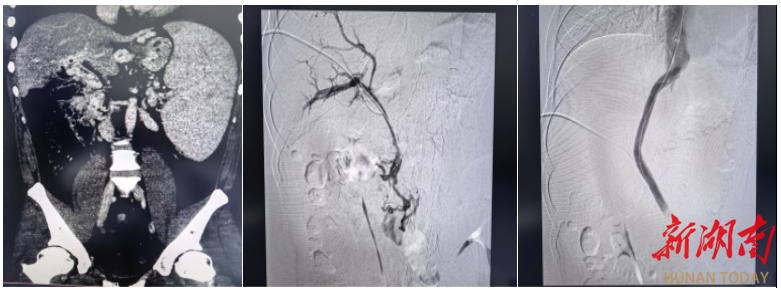

此次手术被业内视为介入领域的“极限挑战”,核心难点在于患者极为罕见的血管条件:门静脉主干完全闭塞,门静脉海绵样变,脾静脉与肠系膜上静脉广泛血栓充填,常规TIPS手术缺乏有效流入道,标准穿刺路径完全失效。在血管解剖结构破坏、解剖标志模糊、血栓弥漫充填的极端条件下,从零构建肝内分流通道,对术者的操作精度、临床经验与应急处置能力均提出极高要求。

“没有通道,我们就为生命开辟一条通道。”面对患者与家属的殷切期盼,梁琪带领吴作为、骆雷等核心团队成员毅然迎难而上。术前,团队反复研读影像学资料,全面评估血管条件与手术风险,制定了周密的个体化手术方案。术中,团队凭借深厚的介入诊疗功底,沉着操控、精准穿刺,在闭塞多年的血管中耐心探查、精细开通,成功将支架置入门静脉主干并建立肝内分流道,显著降低门静脉压力,从根源上解除致命大出血风险,实现微创、安全、高效救治,疗效远超家属预期。